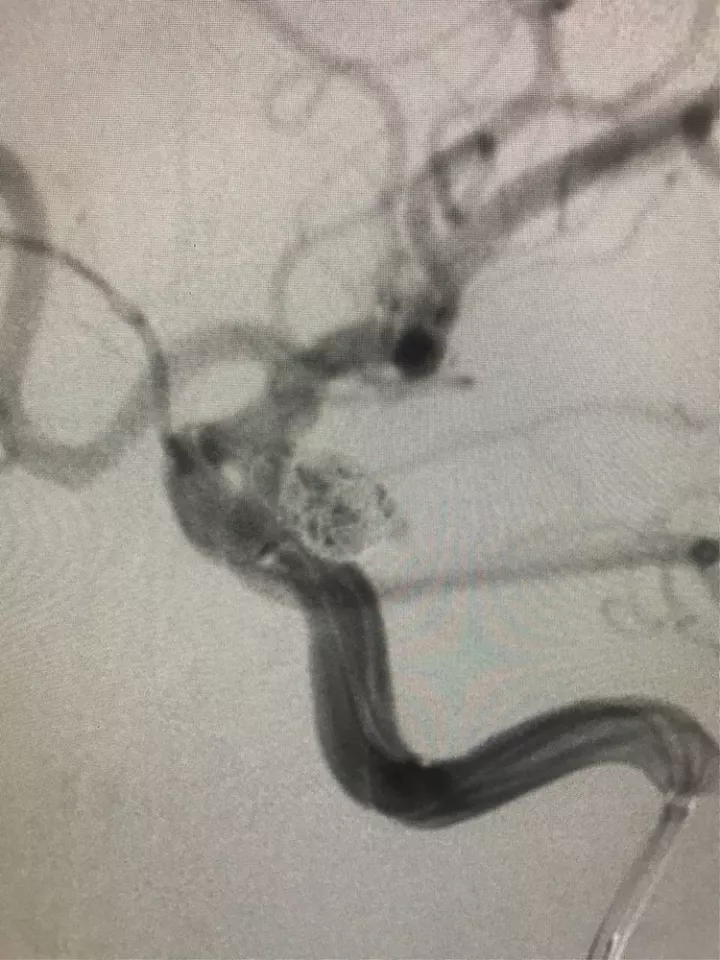

左侧后交通动脉瘤,胚胎型大脑后动脉

3D

局部观,宽颈,涉及颈内动脉和后交通动脉

椎动脉造影见左侧大脑后动脉P1段很细